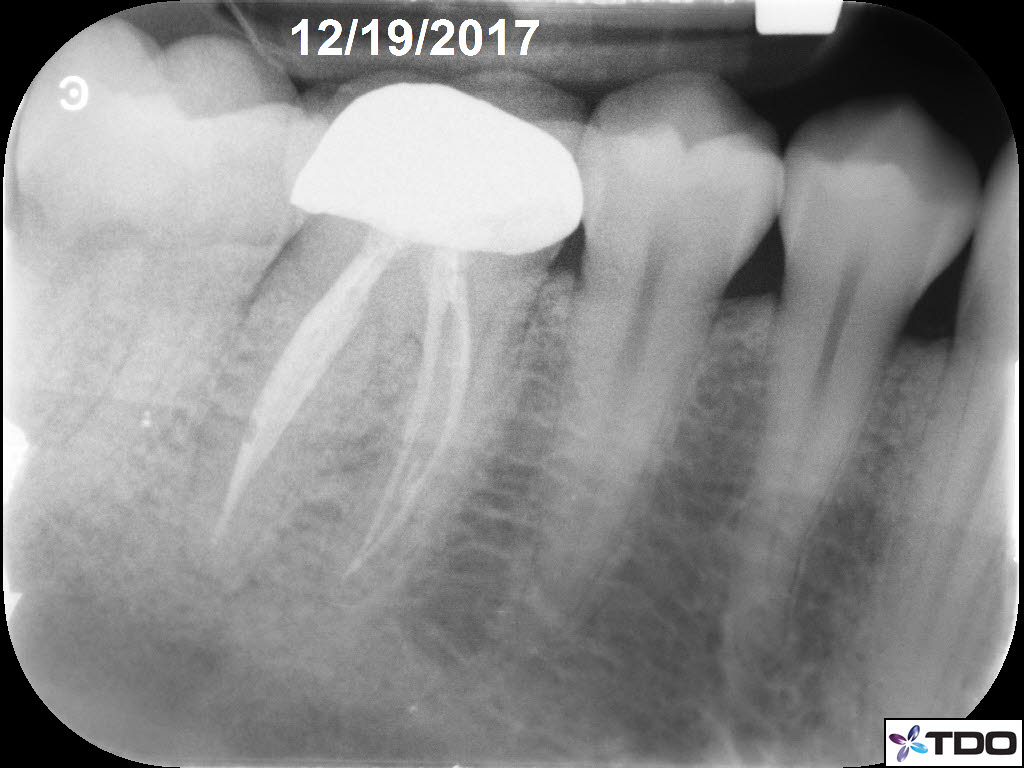

In the hierarchy of dentin conservation the existing restorative has the lowest priority and it quite frankly gets in the way of our access to the root canal system. But, after practicing directed dentin conservation for a while, you sometimes get lucky. The patient is 40yo. She was symptomatic at the time of treatment and interestingly the mesiobuccal canal was partially vital while the mesiolingual, distobuccal and distolingual canals were partially necrotic. She was asymptomatic at the completion visit as well as at the follow-up appointments.

Great insight into the challenges of dentin conservation Dale. The case illustrates the unpredictability of canal vitality and the need for a strategic approach. The 1 year follow up success adds another layer to the discussion. Professional General Contractors in Laval Quebec CA

Great insight into the challenges of dentin conservation Dale. The case illustrates the unpredictability of canal vitality and the need for a strategic approach. The 1 year follow up success adds another layer to the discussion.